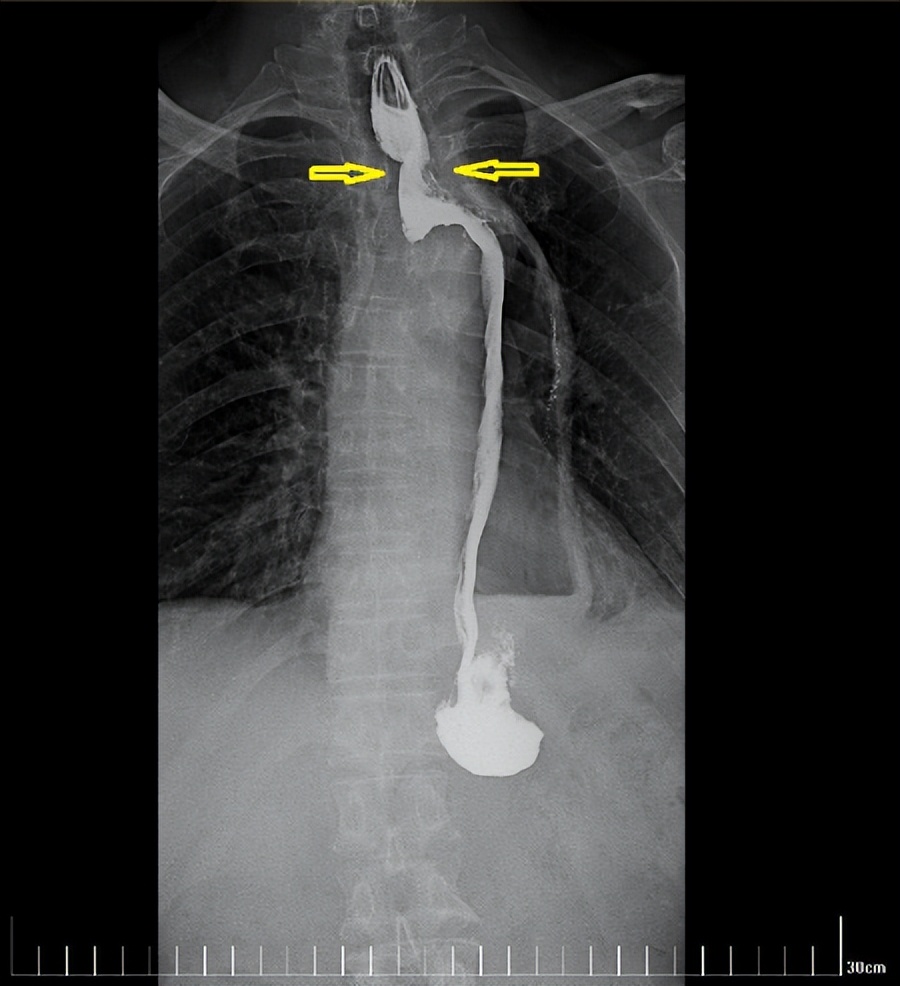

经过一个周期的放疗,李先生明显感受好多了,可以正常吃饭喝水。食管钡餐造影显示,食管吻合口区肿块明显缩小,食管狭窄减轻。

治疗后